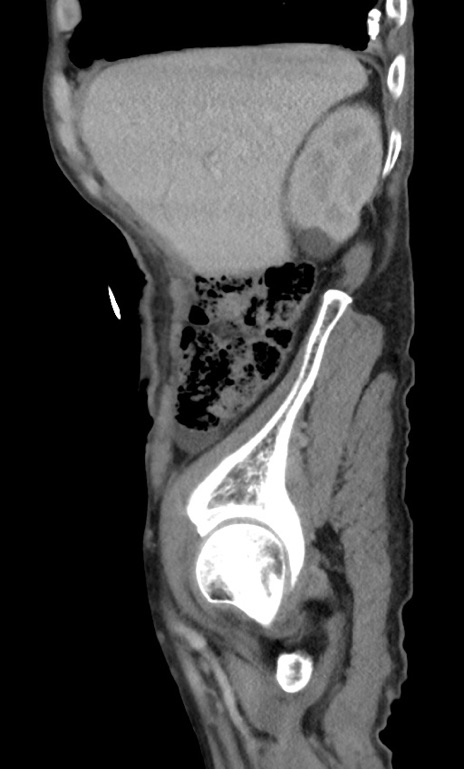

症例3(矢状断像)

【症例】 70歳代男性

【主訴】右鼠径部腫瘤、疼痛

【現病歴】本日朝より上記主訴あり、受診。

【既往歴】膀胱癌にて膀胱全摘、両側尿管皮膚瘻

【データ】WBC 5600、CRP 0.56